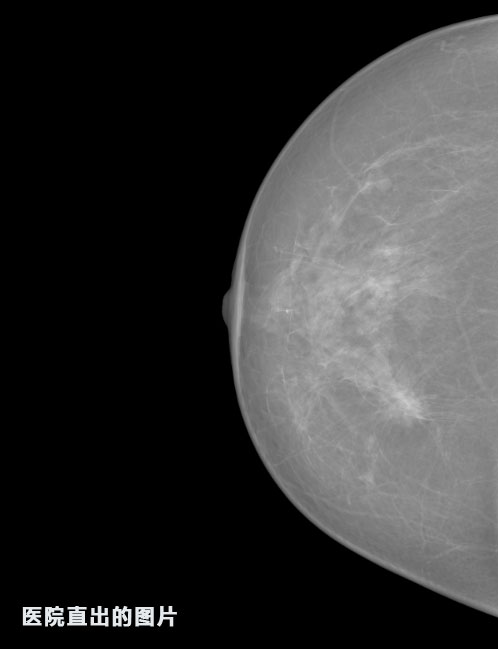

英特健康AI深度學習醫(yī)療圖像識別系統(tǒng)案例_乳腺

01.jpg

識別報告:

1.發(fā)現(xiàn)良性鈣化,可能性為19.88%---位置框指數(shù):[1796.0867 1359.8237 2058.1372 1582.5334]

2.發(fā)現(xiàn)惡意鈣化的可能性為15.18%---位置框指數(shù):[1789.4733 1365.9951 2063.7698 1576.0613]

3.發(fā)現(xiàn)惡意鈣化的可能性為12.45%---位于框指數(shù):[1859.3987 1422.3184 2006.5494 1528.2698]